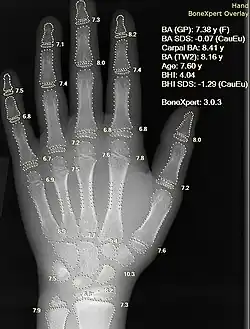

Image and sound processing

Information can take the form of images, sound, video or other multimedia. Bits of information can be streamed via signals. Its processing is the central notion of informatics, the European view on computing, which studies information processing algorithms independently of the type of information carrier – whether it is electrical, mechanical or biological. This field plays important role in information theory, telecommunications, information engineering and has applications in medical image computing and speech synthesis, among others. What is the lower bound on the complexity of fast Fourier transform algorithms? is one of the unsolved problems in theoretical computer science.

|

| FFT algorithms | Image processing | Speech recognition | Data compression | Medical image computing | Speech synthesis |